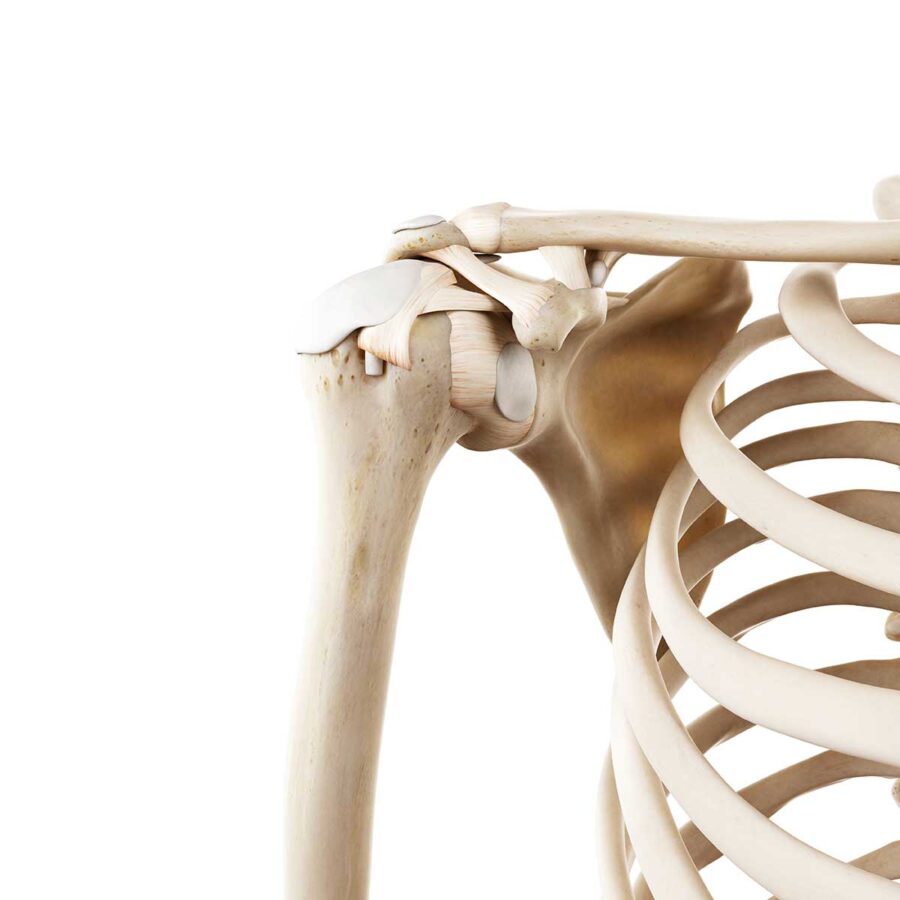

Si le patient continue à ressentir une appréhension ou une sensation d’instabilité, si le patient a un sport ou un métier l’exposant à la luxation, un avis chirurgical est demandé et une imagerie peut être prescrite (IRM, Scanner). Plus le patient est jeune et plus il sera envisagé de stabiliser l’épaule chirurgicalement.